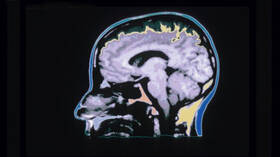

باحثون يكشفون “الأثر الحقيقي” للقلق المقترن بالاكتئاب على أدمغة المرضى!

وُجد أن أدمغة الأشخاص الذين يعانون من ويلات القلق والاكتئاب، تتضخم بشكل كبير، ويقول خبراء إن النشاط غير العادي قد يخفي جزءا من الضرر الذي يمكن أن يسببه الاكتئاب.